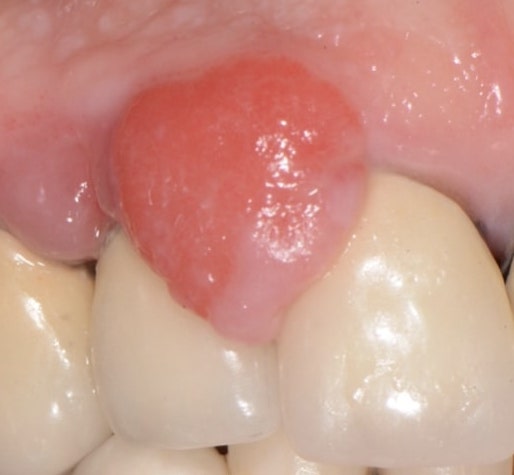

epulide

Gengive

Epulide: i miglioramenti dati dalla terapia igienica

Read More

Epulide protesi fissa

BlogGengive

Come si risolve il problema dell’epulide?